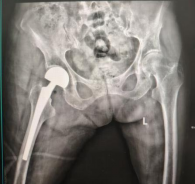

术中,团队采用微创入路,精准植入人工股骨头。手术创伤小、出血少,假体安放位置理想,为快速康复打下了坚实基础。

术后复查的 X 线片显示,两位老人髋关节置换位置均非常理想,为后续康复锻炼提供了必要条件。在医护团队的精心指导和鼓励下,两位老人术后第三天便成功下地站立、行走。